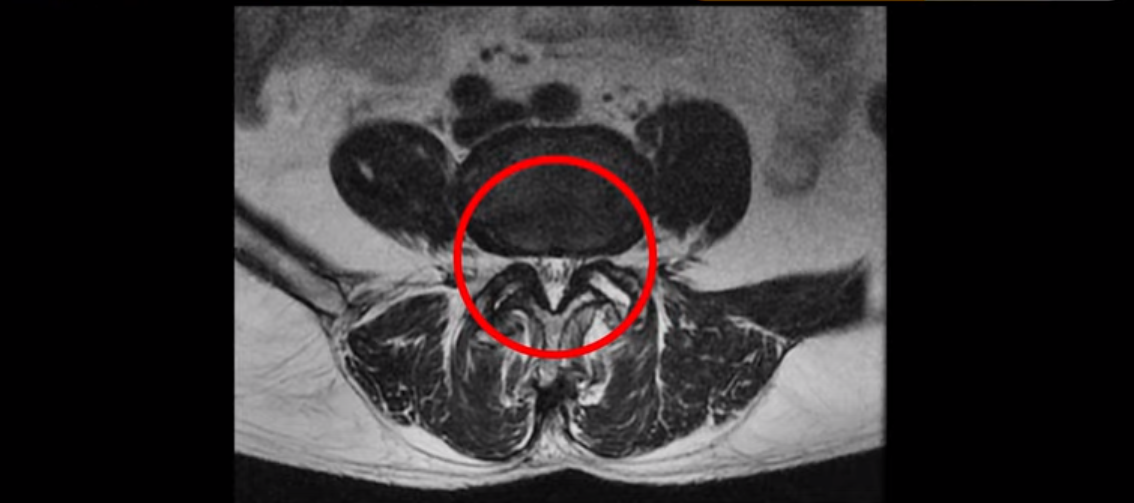

이분 MRI 보면서 설명드린 후 왜 이분처럼 발병한지 얼마 안된 협착증이 치료가 정말 빠르고 쉬운 건지 또 치료는 어떻게 하는 건지 자세히 설명 드리도록 하겠습니다.

MRI를 보면 척추 여러 마디가 퇴행되어 있고

척추관도 좁아져 있고

특히 왼쪽 신경가지가 빠져나가는 4번 5번, 5번 1번 추간공들이 많이 좁아져 있습니다.

그래서 이분은 몇 달 전부터 갑자기 왼쪽 엉덩이부터 발바닥까지 저리고 아픈 증상이 생겨서 걷기도 어렵고 무릎도 차고 시립니다. 그런데 왜 이렇게 얼마 전에 갑자기 발병한 협착증일수록 치료가 정말 빠르고 쉽다는 걸까요?